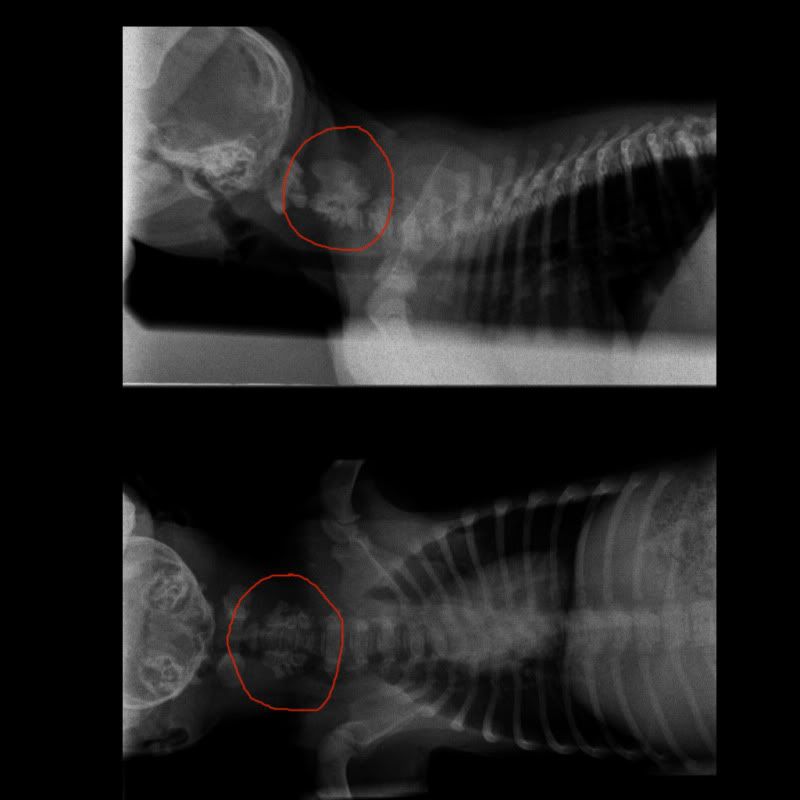

Ik heb vandaag de röntgenfoto via email binnen gekregen van Kaine.

Voor wie interesse heeft, zie de link:

http://img.photobucket.com/albums/v61/stockyrascals/SPINE-CranialCervicalLateraal-03_02_2011-18_08_38-7181.jpg